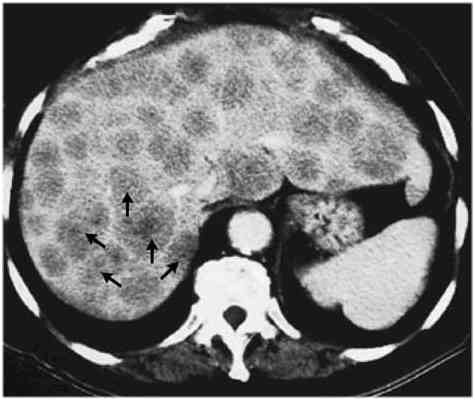

Raziskovalke in raziskovalci so najprej odvzeli maligno tkivo ljudem s tumorjem črevesja in z metastazami v jetrih. Preučevali so, ali se bakterija Fusobacterium nucleatum, ki jo tumorske formacije najpogosteje vsebujejo, pojavlja v obeh tipih tumorjev. Potrdili so svojo domnevo, da se pri večini bolnikov v črevesnem in jetrnem tumorju nahaja isti sev te bakterije. Veljalo je tudi nasprotno; če bakterij ni bilo v črevesnem tumorju, jih ni bilo tudi v jetrnem.

Z združenjem izsledkov prvega in drugega dela študije raziskovalna skupina predvideva, da bakterije potujejo s tumorjem na novo lokacijo in morda tudi pomagajo pri kolonizaciji novega mesta oziroma tvorbi metastaz. Za potrditev ugotovitev ter preučitev delovanja antibiotikov proti nekaterim tumorjem pa bo treba opraviti še dodatne raziskave.